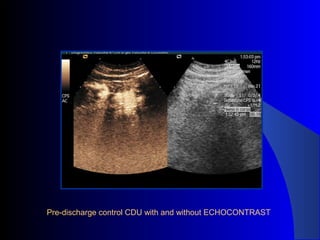

The document discusses the clinical application of the Endurant stent graft system in treating aorto-bisiliac aneurysms, detailing procedures performed on two male patients aged 72 and 73. Each patient had a history of dyslipidemia and carotid atherosclerosis, with procedures involving the bilateral bell bottom technique and the use of coils and fibrin glue. It includes pre-surgery imaging, intrasurgery angiography, and follow-up control scans to monitor outcomes.